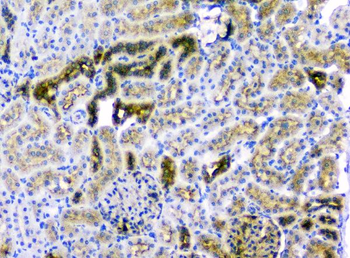

10 μg, 100 μg - Cubilin antibody [orb4997]Featured

ICC, IF, IHC-P, WB

Human, Mouse, Porcine, Rat

Rabbit

Polyclonal

Unconjugated

100 μg - PGP9.5 antibody [orb6713]Featured